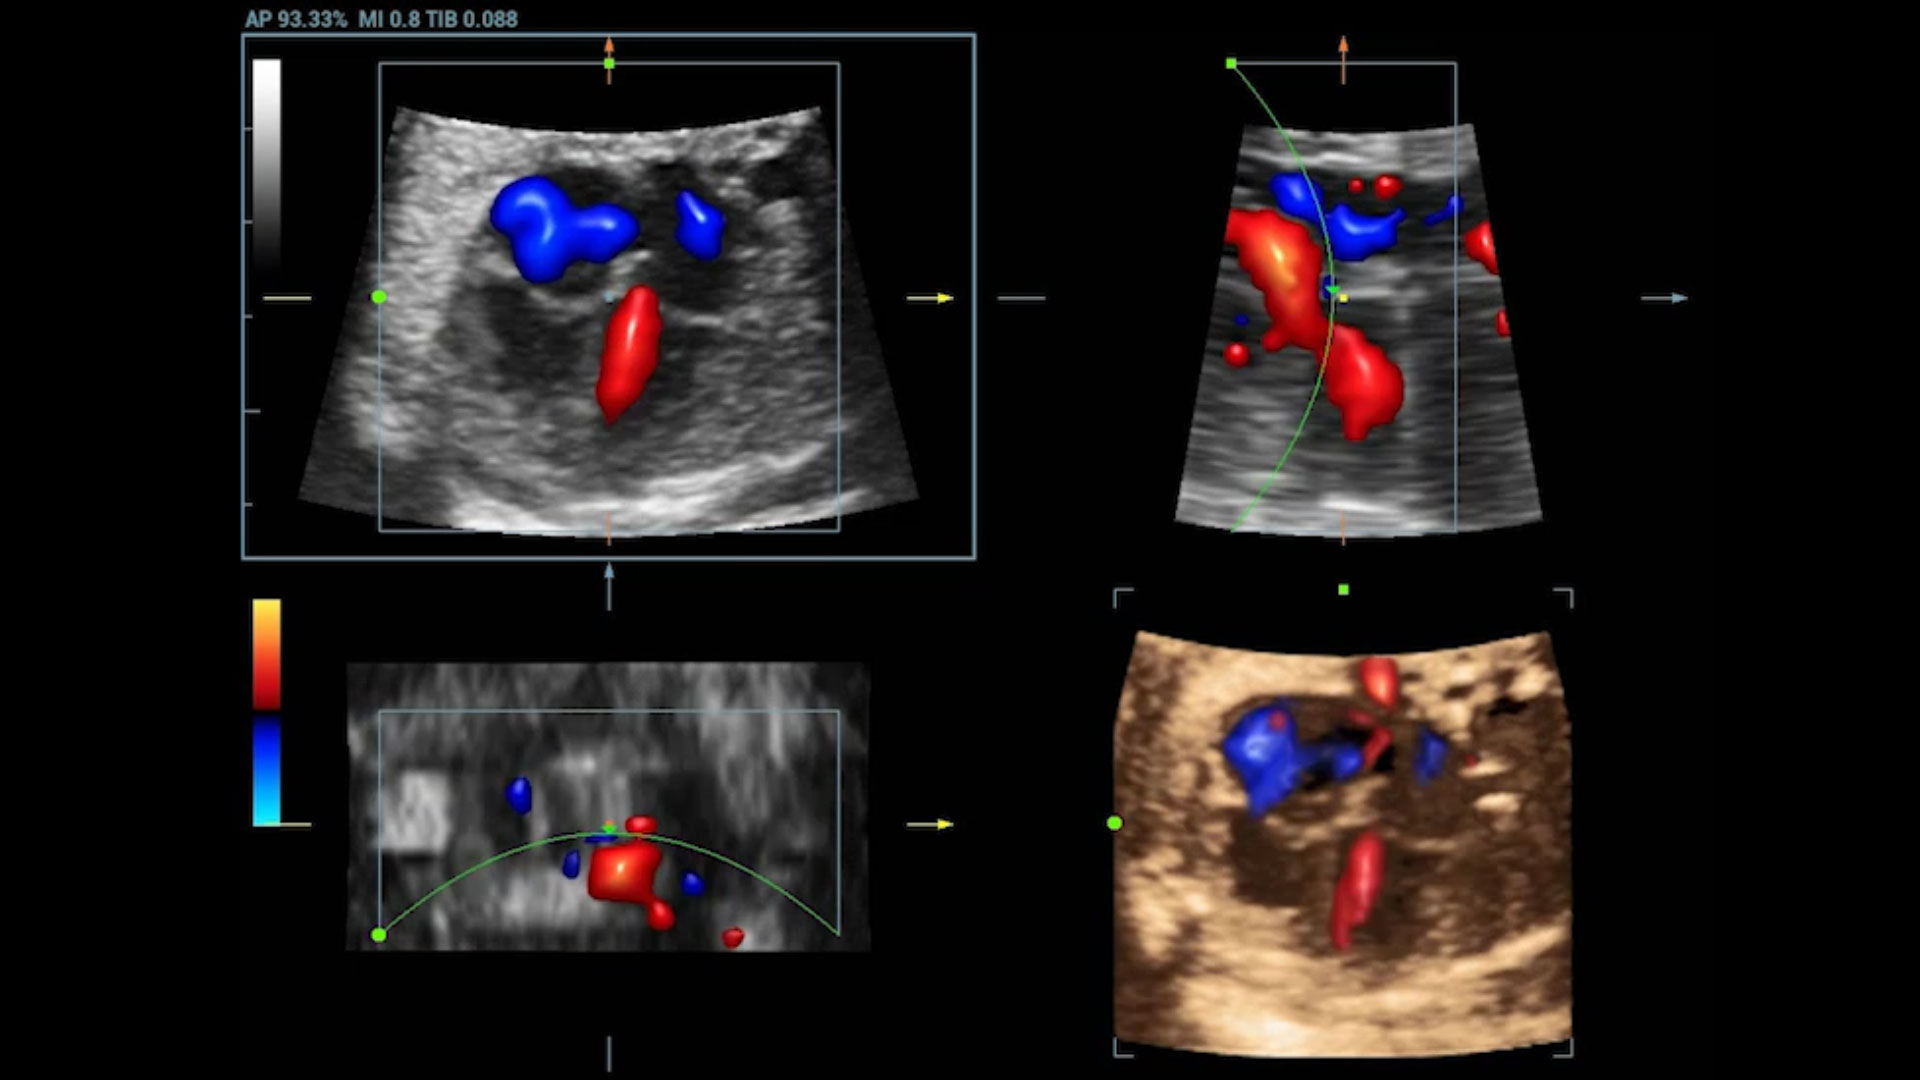

UMA (Ultra-Micro Angiography)

The innovative technology breaks the bottlenecks of traditional Doppler imaging. With ultra-high spatial resolution and flow sensitivity, it allows detecting super-subtle and super-slow flow perfusions, thereby extending the clinical application of qualitative and quantitative ultrasound evaluation in fetal brain, kidney, placenta, endometrium, ovary, etc.

UMA - fetus renal flow

3D UMA - fetus intracranial flow

UMA - uterine and endometrial flow

3D UMA - perifollicular blood flow